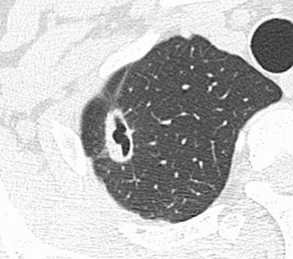

CT所見としては胸膜陥入像を伴う空洞性病変が確認できます。当然悪性腫瘍も鑑別になります。

気管支鏡検査へ進み、肺クリプトコッカス症であった症例でしたが、肺癌であったなら発見が遅れると致命的になります。医師の診断能力と患者の定期的なレントゲン写真撮影が必要になります。